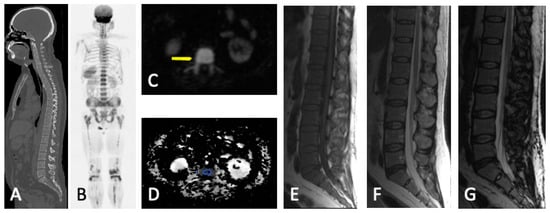

4. WBMRI

4.2. Disease Patterns

- Diffuse pattern: Diffuse disease can be suspected from a diffuse decreased signal on T1WI (either iso- or hypointense to intervertebral discs and muscle) and a diffuse increased signal throughout the marrow on T2FSWI, STIR, or high b-value DWI. Marrow ADC values above 600–700 μm2/s in a nontreated and newly diagnosed patient with MM could be used to increase confidence for the diagnosis of diffuse marrow involvement [33] (Figure 7). Due to potential false-positive findings, diffuse disease in imaging must be supported by bone marrow trephine biopsy [26].